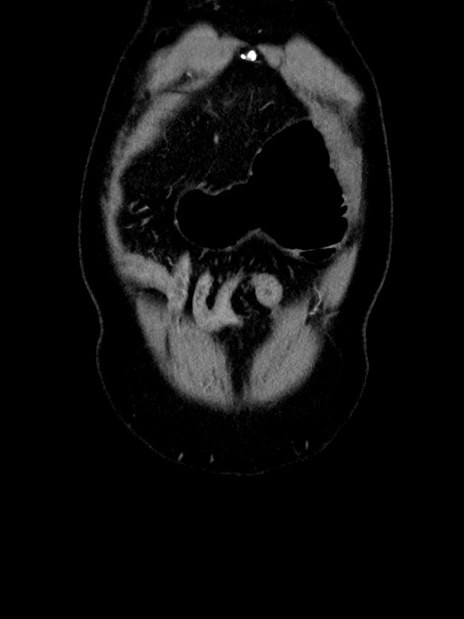

横断像

【症例】70歳代 男性

【主訴】腹部膨満、嘔吐

【現病歴】昨日より腹部膨満感出現。本日増悪し、仙痛出現。嘔吐あり、受診。

【既往歴】糖尿病、胆摘後

【身体所見】BP 149/80mmHg、HR 74/min、BT 35.9℃、腹部:膨満、軟、圧痛なし。腸雑音減弱あり。上腹部正中切開瘢痕あり。

【データ】WBC 13500、CRP 1.72